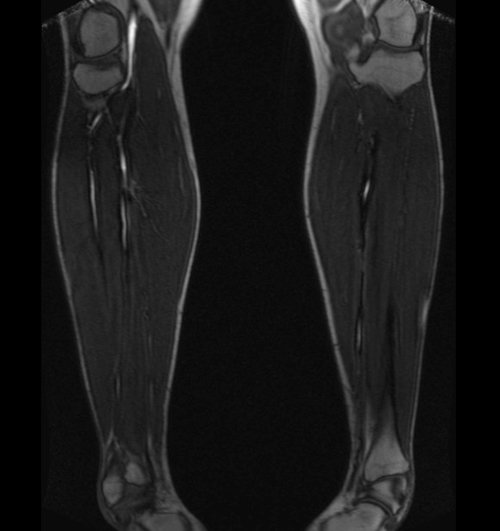

LOWER LEG